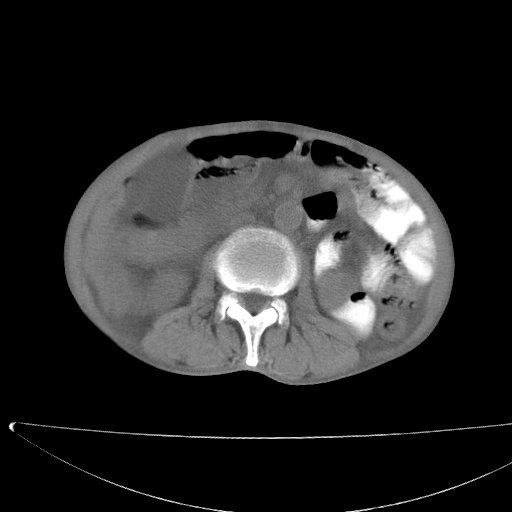

标题: CT17147:男70岁,上腹部不适1月。 [打印本页]

患者男70岁,上腹部不适1月。8年前有胃癌手术史。余病史不祥。

肝门区占位性病变并肝内胆管扩张。

小网膜囊区及腹膜后肿大淋巴结。